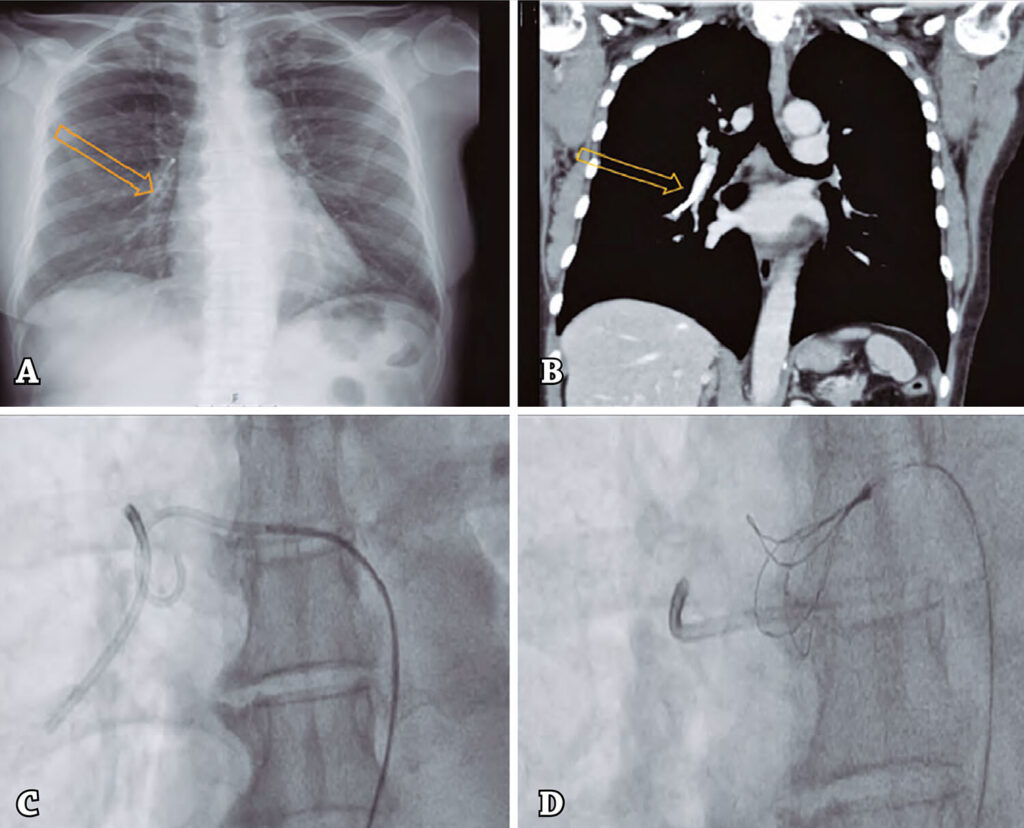

During follow-up in oncology consultation, the patient presented cough and underwent a chest X-ray and thoracic computed tomography that revealed a fracture and embolization of intravascular portion of central venous catheter to the right pulmonary artery (Figures 1A and 1B). The patient was referred to cardiac catheterization lab for percutaneous removal of the intravascular portion of the central venous catheter.

Figure 1

(A) Chest X-ray: intravascular portion of central venous catheter in the right pulmonary artery. (B) Thoracic computed tomography: intravascular portion of central venous catheter in the right pulmonary artery. (C) 5-F pigtail catheter grabbing one of the edges of the catheter fragment. (D) 6-F EN-Snare® catheter that collected catheter fragment.